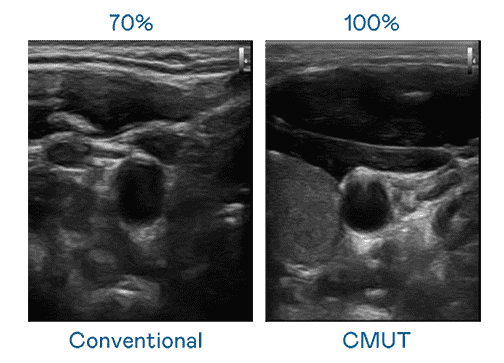

CMUT 技术是一种用电容式微机电元件来产生超音波讯号的技术。。。与传统 PZT 压电式技术相比,,,,CMUT 频宽增加 30%,,,更宽频的超音波讯号让影像解析度大幅提升,,是实现高影像品质医疗超音波扫描、、、促进精准医疗发展的关键技术。。。。

超音波影像的解析度高低,,,,首先取决于探头能发出的讯号频宽。。。。人生就是博 CMUT 可提供高清晰的超音波讯号,,提供高频宽、、、、高灵敏度、、、影像纹理细节更高的超音波影像,,,,协助医护人员缩短影像判读时间及利用精准的医疗影像进行诊断。。。。